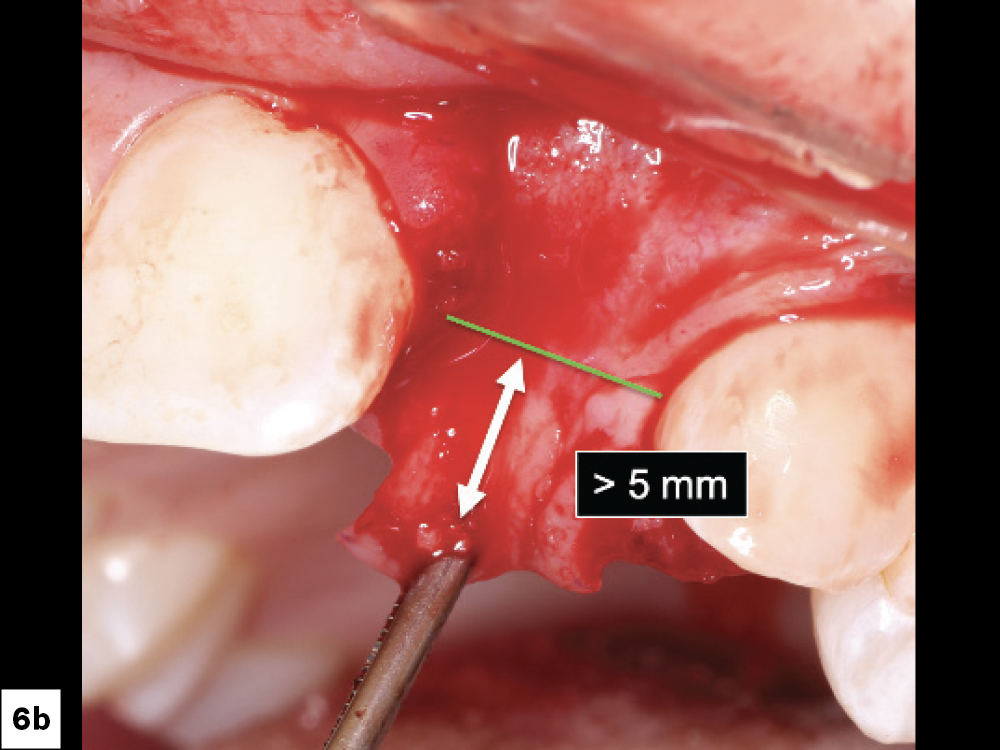

Excessive flap tension is a leading cause of ILO. This can be prevented by appropriate incision and flap design and periosteal releasing incisions. Clinicians should utilize relieving procedures (i.e., periosteal and blunt dissection) in order to reduce the tension on the incision line. Ideally, the flap should be able to be stretched a minimum of 5 mm past the incision line. Insufficient soft tissue mobility or excessive tension on the tissues during the healing phase may lead to loss of approximation of the tissue margins (Figs. 5a, 5b, 6a, 6b).

Tension Free Tissue: (a) Reduction of tissue tension, (b) Ideally tissue should be able to be re-approximated more than 5 mm across the suture line.

Figures 6a, 6b: Tension Free Tissue: (a) Reduction of tissue tension, (b) Ideally tissue should be able to be re-approximated

more than 5 mm across the suture line.